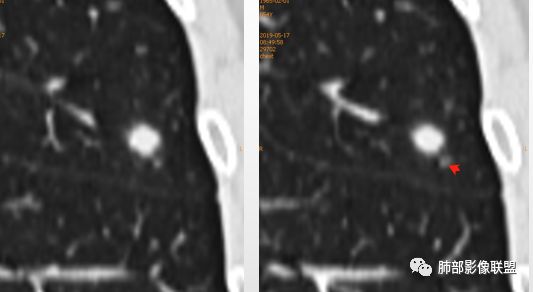

划重点:1、胸膜下、两下肺多见。

2、“3个1/3”:1/3与胸膜相连,1/3内部可见空泡征,1/3有晕征

3、“2个2/3”:2/3与胸膜有间隙,2/3近段与血管相连。

1、与炎性假瘤、恶性肿瘤鉴别:恶性肿瘤边缘膨隆,收缩也是毛毛糙糙的,炎性假瘤收缩力较强,边缘凹陷的多。隐球菌孤立结节收缩力弱,膨胀力也弱,与胸膜关系多为糊墙,部分有间隙。右边两幅可以看到胸膜增厚,胸膜下脂肪间隙增宽。晕中长毛刺,边缘平直,血管走行自然,鉴别肺癌。